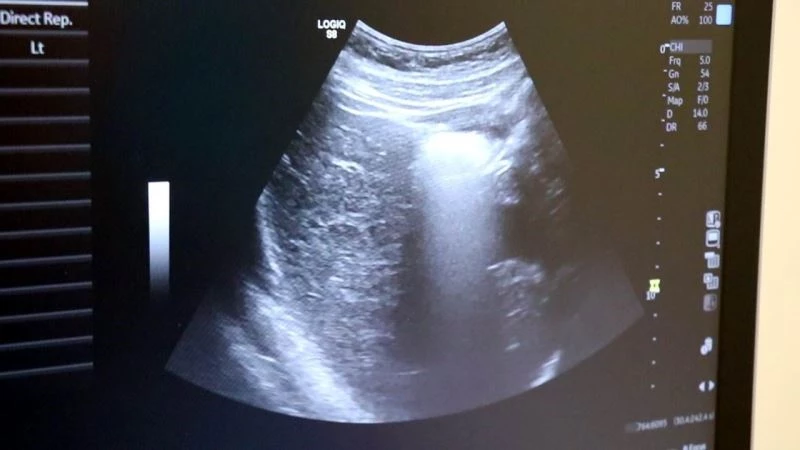

Ultrason uzun zamandan beri özellikle gebe annelerde sıklıkla başvurulan bir görüntüleme yöntemi. Yüksek ses frekanslarının işlenip ekrana yansıtılması ile elde edilen görüntülerle bebeğin sağlık durumunun yanı sıra birçok bilgiye de ultrason sayesinde erişmek mümkün olabiliyor. Medicana International Samsun Hastanesi Radyoloji Uzmanı Dr. İlker Eroğlu, 2 boyutlu ultrasonun ve 4 boyutlu ultrasonun hiçbir zararı olmadığını belirterek açıklamalarda bulundu.

Ayrıntılı ve 4 boyutlu ultrason ile bebeklerin doğmadan önceki sağlık durumlarının belirlenebileceğine değinen Uzm. Dr. İlker Eroğlu, “Ultrason; yüksek frekanslı ses dalgalarının bilgisayar işlemcisinde işlenip, kablo arayıcılığıyla monitöre aktarılmasıdır. Son yıllarda gebelikte ayrıntılı ultrason gerekliliği giderek artmaktadır. Yaklaşık 50 yıl önce ultrason yaygın değilken doğumlarda bebek nasıl doğacak, sağlıklı mı sağlıksız mı doğacak ya da cinsiyet bile bilinemiyordu. 4 boyutlu ultrasonda ya da ayrıntılı ultrasondan sonra bebeğin sakatlıkları doğumdan önce anlaşılıp, tedavisi mümkün olanlar da doğumdan önce tedavi edilebilir oldu. Böylelikle bebeklerin daha sağlıklı olarak dünyaya gelmesi sağlanmış oldu. O nedenle ayrıntılı ultrason gereklidir” dedi.

Renkli ultrasonlarda bebeklerin anne karnındayken sakatlığı olup olmadığının belirlendiğini ifade eden İlker Eroğlu, “4 boyutlu ultrason halk arasında ‘renkli ultrason’ diye bilinir. Anneler bu ultrasonda bebeğin görüntüsünü anladığı için onu daha çok sever. Hekimler genelde ultrasona siyah-beyaz bakar. 4 boyutlu ultrason iç organlar hakkında detaylı bilgi vermez. Biz detaylı ultrasonda (2. düzey ultrason) bebeğin iç organlarına yönelik incelemeyi siyah beyaz olarak yaparız. O nedenle bizim için siyah-beyaz ve 2 boyutlu olarak yapılan inceleme daha önemlidir. 4 boyutlu ultrasonda da faydalandığımız yerler vardır. 4 boyutlu ultrasonda örneğin; bebeğin kolu-bacağı yoksa, dudak yarığı varsa, gösterebiliriz. Çeşitli anatomik deformasyonları da anneye gösterebiliriz. Hala dünyada ayrıntılı ultrason 2 boyutlu ve siyah-beyaz olarak yapılır” diye konuştu.

Uzun yıllardır ultrasonun kullanıldığını ve bir zararının saptanmadığını belirten Dr. Eroğlu, “Ultrason dünyada çok uzun yıllardır kullanılan bir görüntüleme yöntemi. Bizim kulağımızın duyamayacağı yüksek frekans ses dalgaları ile çalışır. Uzun yıllardır kullanılan ultrasonun hiçbir zararının olmadığı görülmüştür. Hastalarımız gönül rahatlığıyla ultrason yaptırabilir. Detaylı ultrason, 2. düzey ultrason, 4 boyutlu ultrason; bunların hepsi aynı işlem. Normalde dünyada 18-22’inci haftalar arasında yapılır ancak klinik tecrübemiz gereği 21 ya da 22. haftada bakmayı tercih ederiz” şeklinde konuştu.